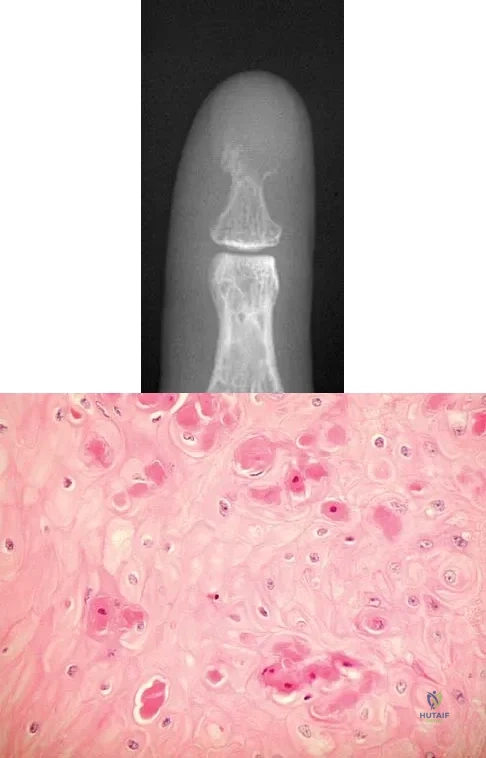

Question 72

A 60-year-old man has pain at the tip of the index finger. A radiograph and biopsy specimen are shown in Figures 40a and 40b. Management should consist of

Explanation